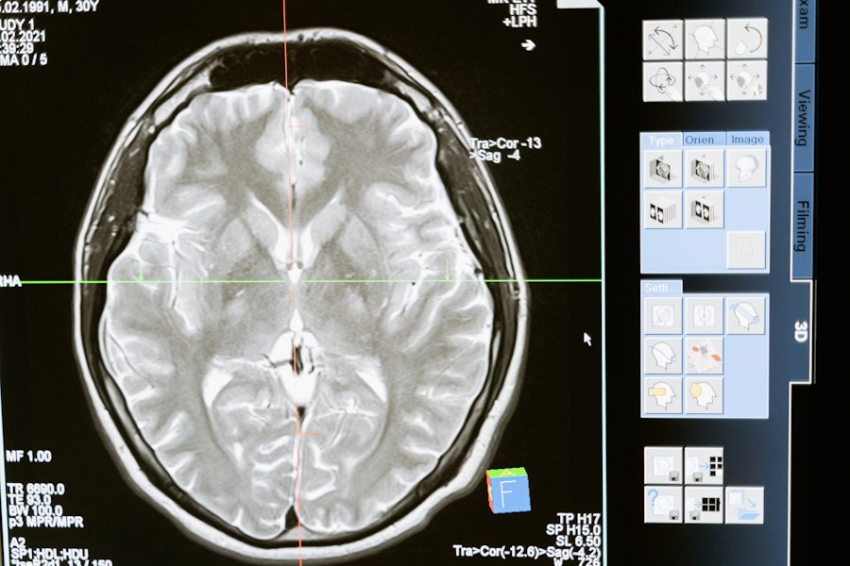

В уникальном эксперименте исследователи смогли продемонстрировать, что гиппокамп - структура в мозге, ответственная за вспоминание и воображение - может быть подчинена воле. Крысы, используя интерфейс "мозг-машина", смогли волевым образом манипулировать своими воспоминаниями и представлениями.

Согласно сообщению на портале Science, гиппокамп играет ключевую роль в формировании и извлечении памяти о людях, событиях и местах, включая пространственные представления. Однако долгое время оставалось неясным, можно ли сознательно управлять этими "картами" памяти. Именно здесь появляется интересное открытие: крысы, используя специально созданный интерфейс, смогли не только активировать определенные воспоминания, но и направлять их в конкретные точки виртуальной реальности.